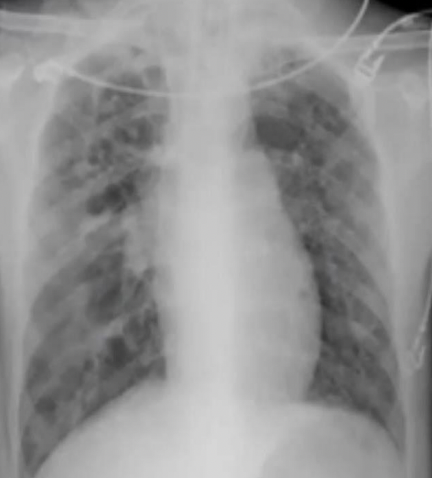

qué se observa en una rx de torax con Tb?

A

Q

qué se observa en una TAC con Tb?